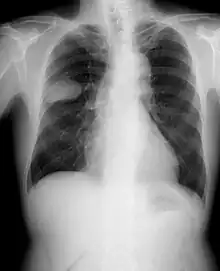

Frontal chest X-ray showing a probable S2–S3 small cell carcinoma in the right side lung.

Small-cell carcinoma of the lung usually presents in the central airways and infiltrates the submucosa leading to narrowing of bronchial airways. Common symptoms include cough, dyspnea, weight loss, and debility. Over 70% of patients with small-cell carcinoma present with metastatic disease; common sites include liver, adrenals, bone, and brain.[19][20]